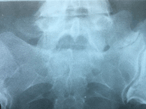

Bertolotti’s syndrome: an underdiagnosed cause for lower back pain

Francisco Alonzo and others

Journal of Surgical Case Reports, Volume 2018, Issue 10, October 2018, rjy276, https://doi.org/10.1093/jscr/rjy276